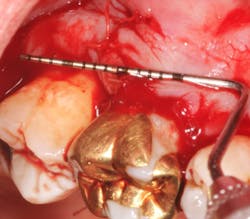

A SECT graft was harvested from the palate (figure 5), and a periosteal-releasing incision was made to ensure flap advancement (figure 6). The SECT graft was secured on the facial of Nos. 2 and 3 with 4-0 chromic gut sutures (figure 7). The osseous defect was then grafted with mineralized cortico-cancellous particulate allograft (Puros, Zimmer Biomet Dental) and covered with a collagen membrane (Bio-Gide, Geistlich Biomaterials; figures 8a and 8b). The flap was coronally advanced to completely cover the hard- and soft-tissue graft and secured with 4-0 chromic gut sutures (figure 9). The palatal donor site was sutured with 4-0 chromic gut sutures as well (figure 10).